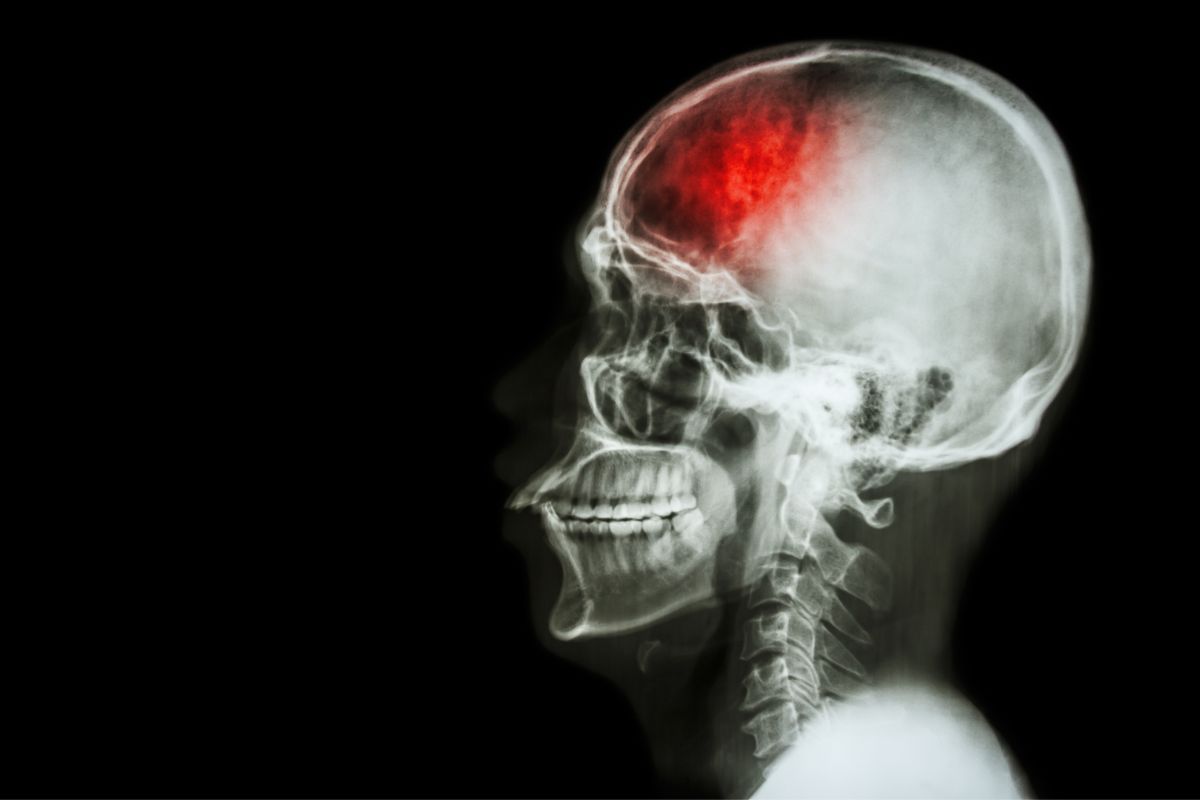

Według danych Narodowego Funduszu Zdrowia, w 2022 roku w Polsce odnotowano blisko 74 tysiące udarów niedokrwiennych mózgu, z czego zdecydowaną większość stanowiły udary pierwszorazowe. Z innych ważnych, chociaż równie niepokojących liczb: 20 proc. osób, które udar przeżyły, wymaga stałej opieki, a 30 proc. takich pacjentów umiera w ciągu roku od stawienia się z udarem do szpitala.

Sam zapewne przyznasz, że wszystkie znaki na niebie i ziemi zdają się nam przypominać — a wręcz wykrzykiwać — że odpowiednia profilaktyka udarowa to coś więcej, niż dbanie o siebie. To obowiązek każdej osoby, która chce żyć w zdrowiu jak najdłużej. Z tego też powodu profesor Alexandru-Vladimir Ciurea, światowej sławy rumuński neurochirurg, dokładnie wyjaśnił, jakie czynności sprawiają, że ryzyko udaru zostaje stłamszone. Bardzo wiele zależy od tego, co jemy i pijemy, dlatego czytaj uważnie. To prostsze niż myślisz i ważniejsze niż cokolwiek innego.